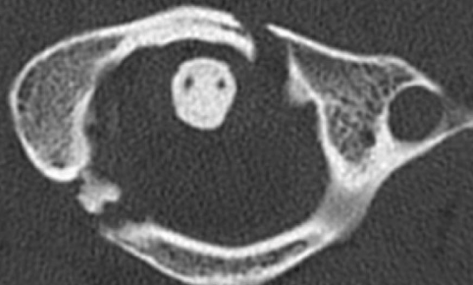

Jefferson fracture- C1 burst fracture

Mechanism: axial load